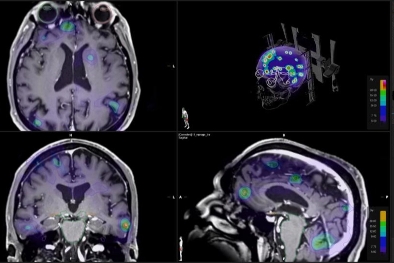

Además, todos los casos tratados son revisados mediante un proceso de revisión por pares (peer review), esto permite que las indicaciones clínicas y planificaciones sean evaluadas en un tumor board antes de iniciar el tratamiento. Utilizamos imágenes de resonancia magnética de alta calidad para asegurar que cada detalle sea considerado en el plan de tratamiento, lo que respalda nuestra precisión y cuidado.

La Radiocirugía Estereotáctica (SRS) es un tratamiento avanzado y preciso utilizado para tratar lesiones intracraneales, realizado por un equipo multidisciplinario que incluye un radio-oncólogo y un neurocirujano acreditado en radiocirugía. Esta técnica permite aplicar radiación de alta precisión directamente sobre el tumor en el cerebro, minimizando el impacto en los tejidos sanos circundantes.

Previo a la primera sesión acudes a una cita para diseñar e individualizar tu tratamiento a través de la simulación y planeación. El objetivo de la simulación es determinar en un equipo de tomografía (TAC simulador) que será lo óptimo para las sesiones de tu curso terapéutico. En esta primera sesión podemos obtener imágenes de tomografía computada que proporcionan información detallada de la localización, el volumen, estructuras que rodean al tumor, etc. Todos estos datos se envían vía red al planificador de tratamiento cuyo software o programa de planeación reconstruye un modelo computacional de tu lesión o lesiones. Sobre este modelo virtual los físicos médicos y dosimetristas delimitan los volúmenes blancos y los órganos de riesgo (tejidos sanos circundantes), calculan las dosis precisas y las direcciones de los haces de radiación que se apuntarán al tumor, y junto con tu radio-oncólogo, definen el plan de tratamiento específico que será enviado al acelerador lineal sin capacidad de modificaciones y con control detallado.

Radiocirugía

Es una cirugía virtual, un procedimiento no-invasivo que no requiere de anestesia en el cual el tejido tumoral es destruido o eliminado por medio de la radiación. Se administran altas dosis con mayor rapidez, acortando el tiempo de la radiación y con precisión submilimétrica, reduciendo la exposición de órganos sanos. Requiere de menos sesiones (de 1 a 8 sesiones) de tratamiento que los otros tipos de radioterapia.

Radiocirugía intracraneal, conocida por sus siglas en inglés SRS o Stereotactic radiosurgery, y la Radiocirugía corporal conocida por sus siglas en inglés SBRT o stereotactic body radiotherapy.

Tenemos experiencia en el tratamiento de oligometastasis (enfermedad metastásica pequeña en número y tamaño), en la cual el tratamiento muy selectivo y preciso con radiocirugía ha demostrado beneficio, además de poderse tratar varias lesiones a la vez.

Radiocirugía intracraneal